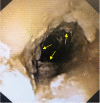

Intermittent treatment response of the mediastinal tumor mass on crizotinib, as seen on chest x-ray. A) Apical (AP) chest x-ray before administration of crizotinib; B) Stable disease after 7 days of daily crizotinib (oral capsules) on AP chest x-ray; C) Improved anti-tumor effect on day 28 after 14 days of crizotinib via nasogastric tube and intravenous vinblastine.

Esophageal crizotinib crystal residue on gastroscopy and reported after a tissue biopsy.